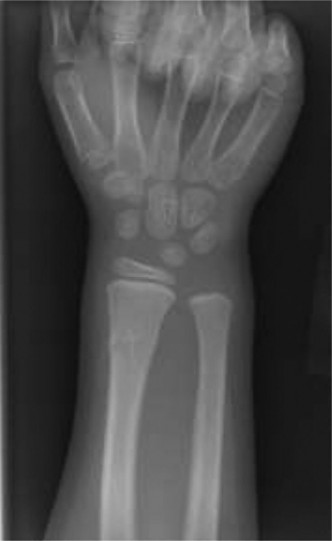

A 44-year-old, right-hand-dominant male with well-controlled diabetes and hypertension presents to clinic wit…